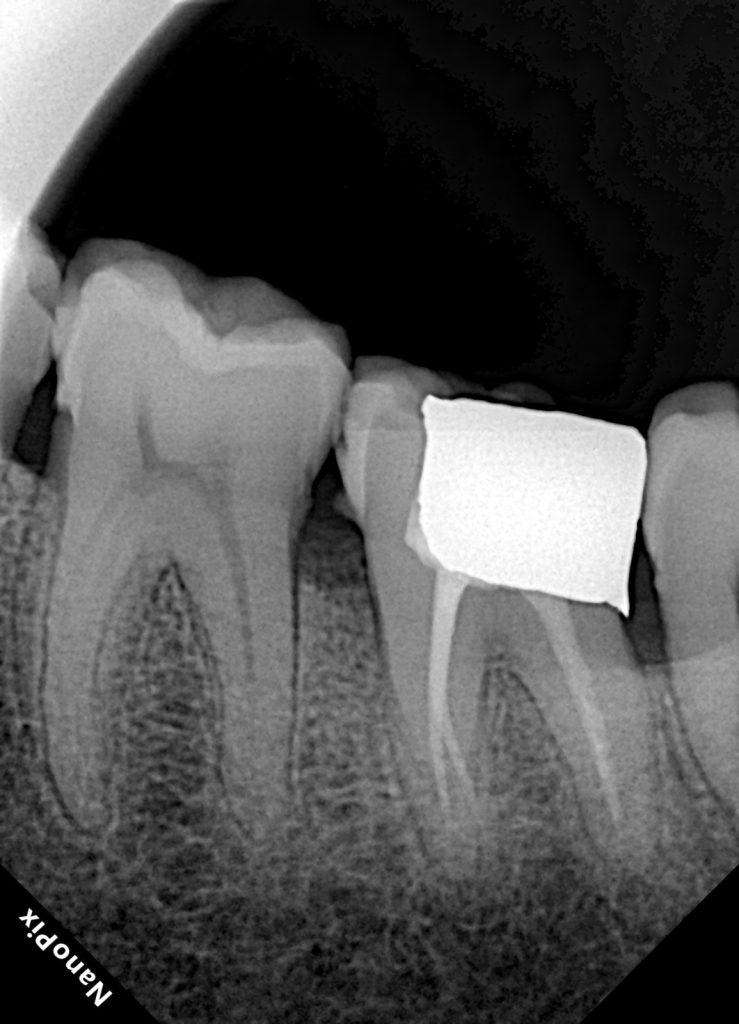

1. Pre-operative Evaluation

The tooth presented with:

- A large, deteriorated amalgam filling

- Recurrent deep caries

- Structural cracks undermining both cusps

- Radiographic involvement suggesting pulpal disease

Diagnosis:

Irreversible pulpitis with structural compromise requiring endodontics and cuspal coverage.

Radiographic results confirmed proper taper, length, and absence of voids.